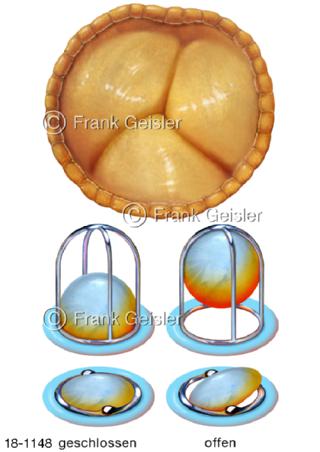

18-1148 Aortenklappe, künstliche Herzklappen